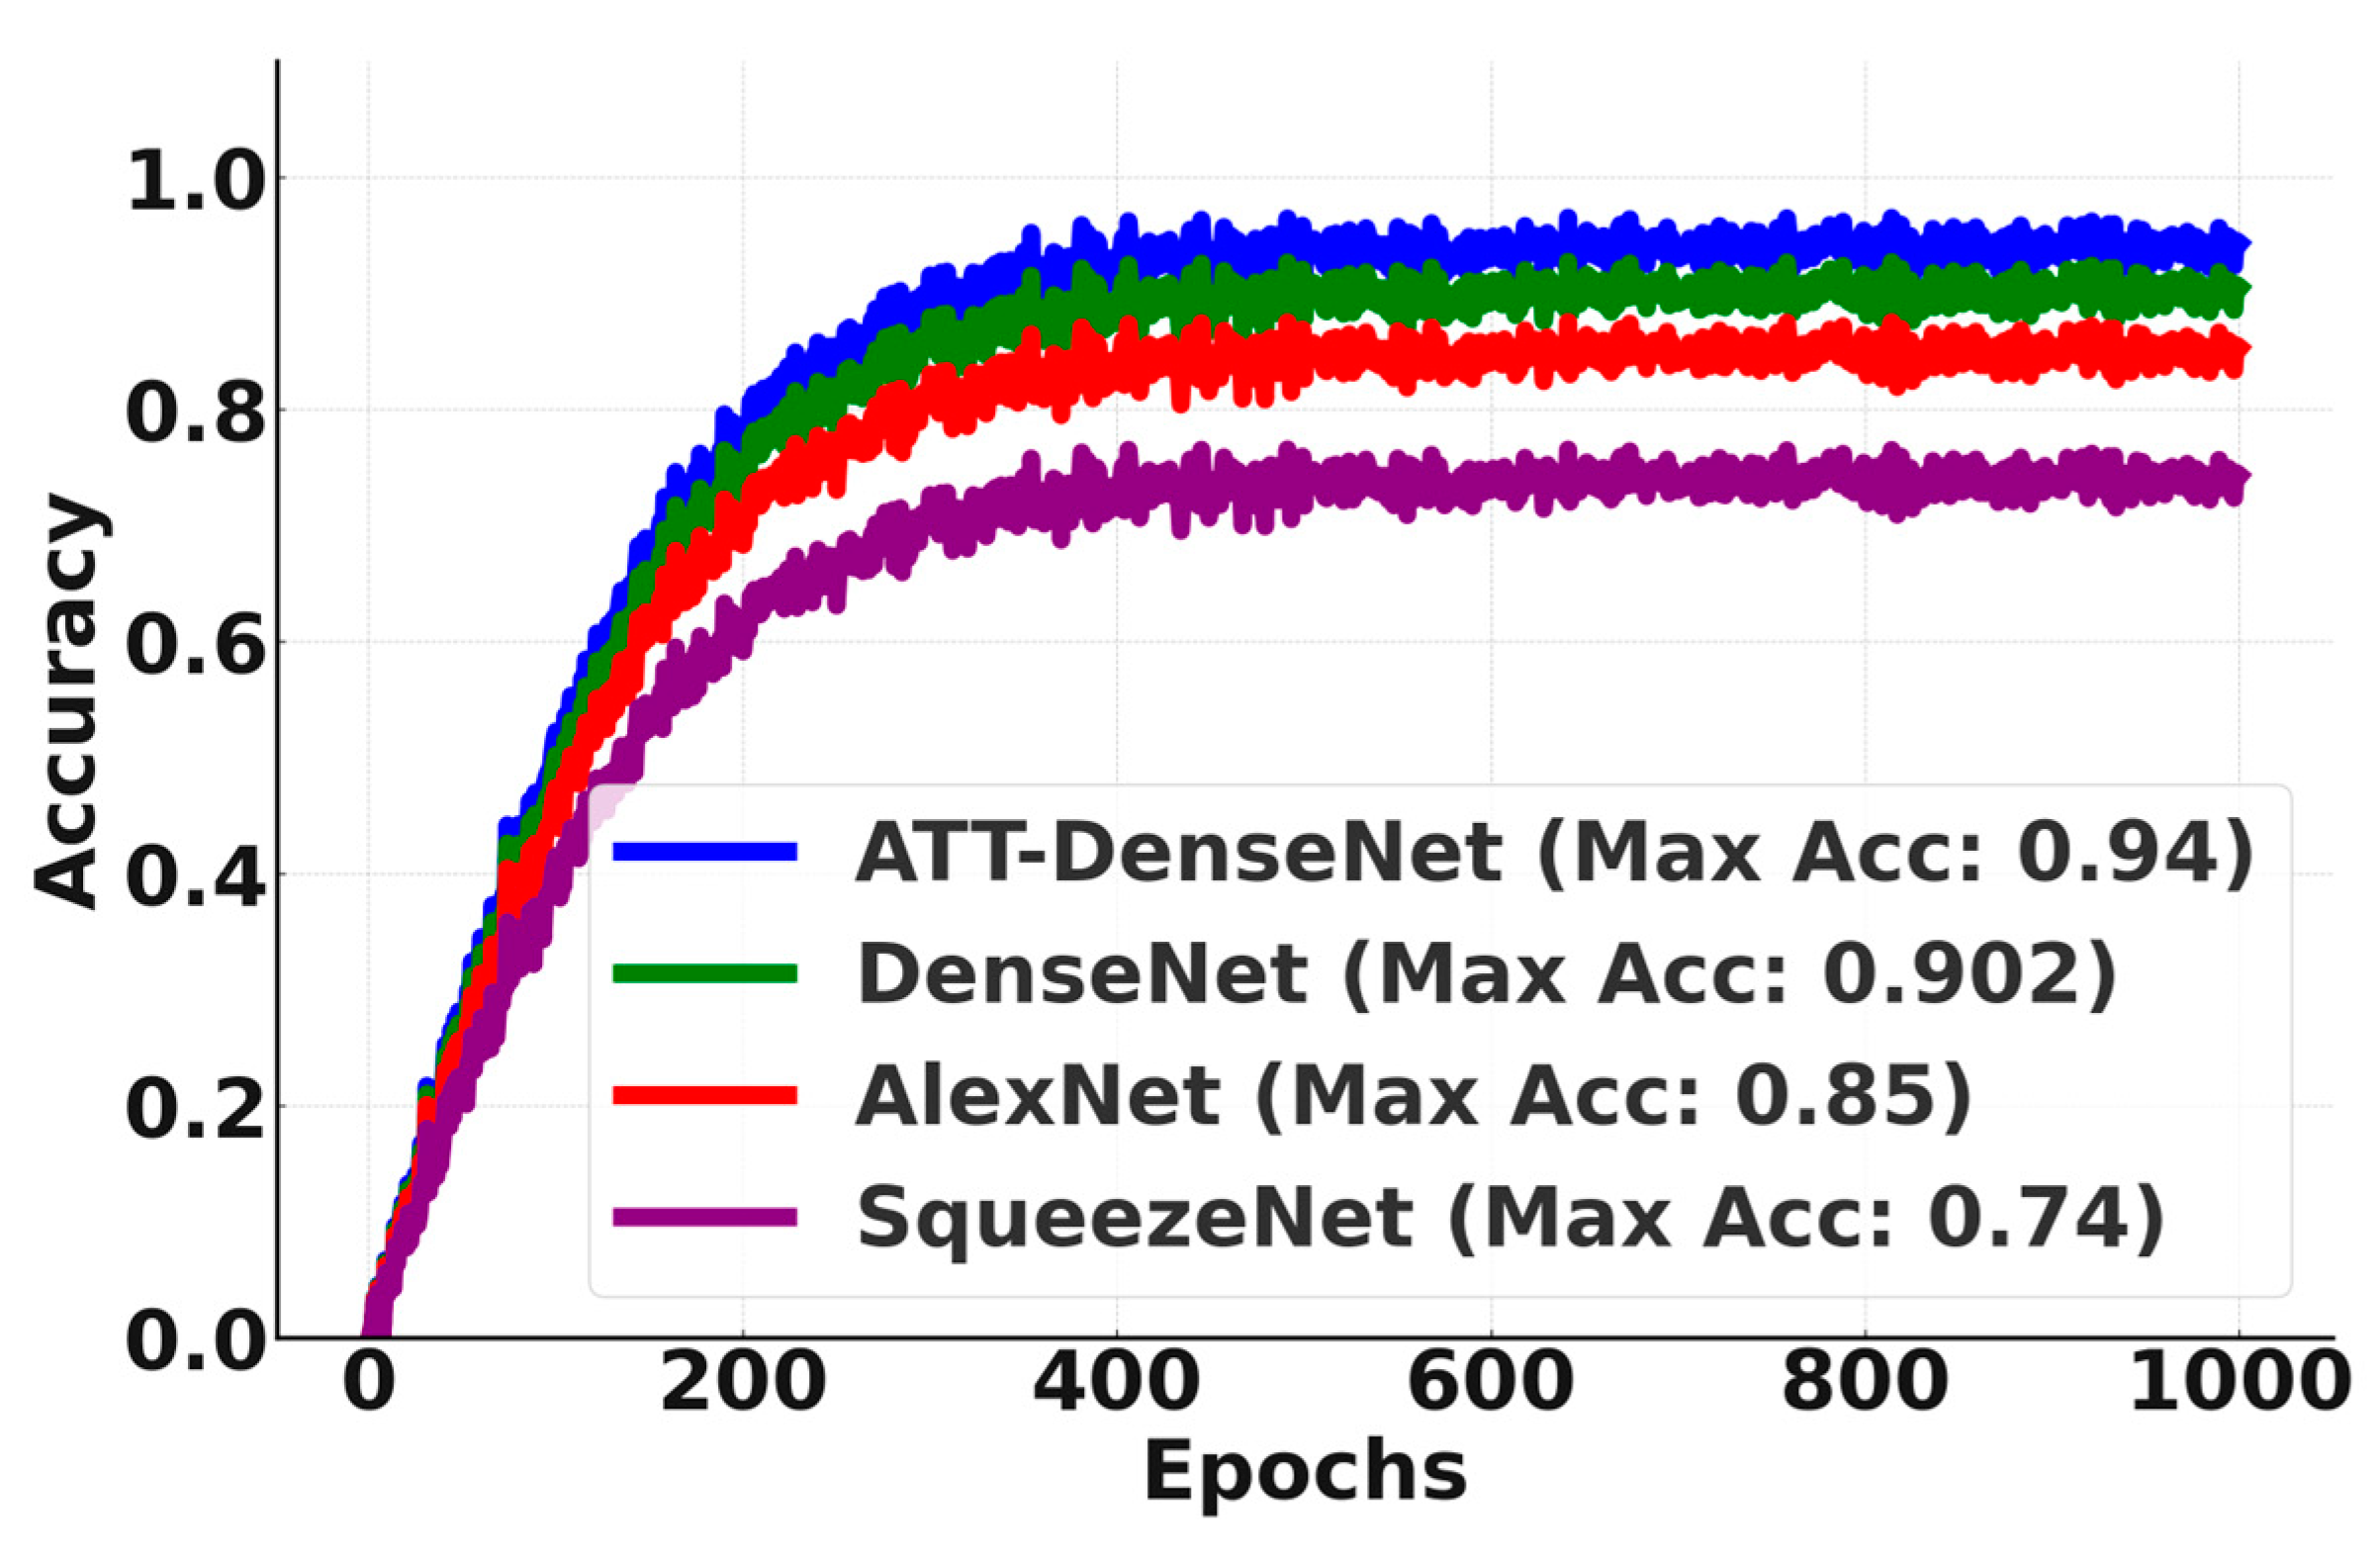

Finally, to show the better performance of ATT-DenseNet in a more vivid way,

Figure 8 presents a comparison of the accuracy curves over 1000 epochs. As we can see from the figure, it outsmarts the baselines by significant margins, achieving an average accuracy of 0.954 (95.4 in percentage).

Figure 10 presents an accuracy curve comparison.

We can see from

Figure 10 that the proposed ATT-DenseNet achieves higher accuracy compared to all the baselines by achieving 94% average accuracy on the test set of the data. Similarly, as presented in terms of histopathological images, the F1-score of ATT-DenseNet is found to be higher than all the other baselines for CT scan images. Finally, we compare the proposed method with RestNet in terms of accuracy and the F1-score and see that the proposed method performs better as well.

The proposed ATT-DenseNet mechanism adaptively recalibrates feature responses by explicitly modeling interdependencies between channels. This means that the method can dynamically emphasize informative features while suppressing irrelevant ones. By contrast, DenseNet without attention, SqueezeNet, and AlexNet lack such mechanisms to focus on the most relevant features, potentially leading to suboptimal feature utilization. Furthermore, the proposed ATT-DenseNet facilitates better discrimination of features by learning channel-wise relationships. By selectively emphasizing important features, the method can potentially enhance the discriminative power of the network, leading to improved classification performance. DenseNet without attention, SqueezeNet, and AlexNet do not have the capability to learn such discriminative features effectively. The adaptive nature of ATT-DenseNet allows the method to dynamically adjust feature importance based on the input, leading to improved generalization across the datasets and scenarios. This adaptability enables our model to capture complex patterns in the data more effectively compared to the fixed feature mappings of DenseNet without attention, SqueezeNet, and AlexNet. DenseNet’s dense connectivity pattern enables feature reuse throughout the network, leading to parameter efficiency. This means DenseNet requires fewer parameters compared to ResNet or traditional architectures to achieve similar or better performance. With fewer parameters, DenseNet models can be trained faster and require less memory. DenseNet’s dense connections facilitate a direct gradient flow from the later layers to the earlier layers during backpropagation. This helps alleviate the vanishing gradient problem, making it easier to train very deep networks. That is why, as presented in

Figure 8,

Figure 10 and

Figure 11, we achieved better accuracy for the proposed ATT-DenseNet.